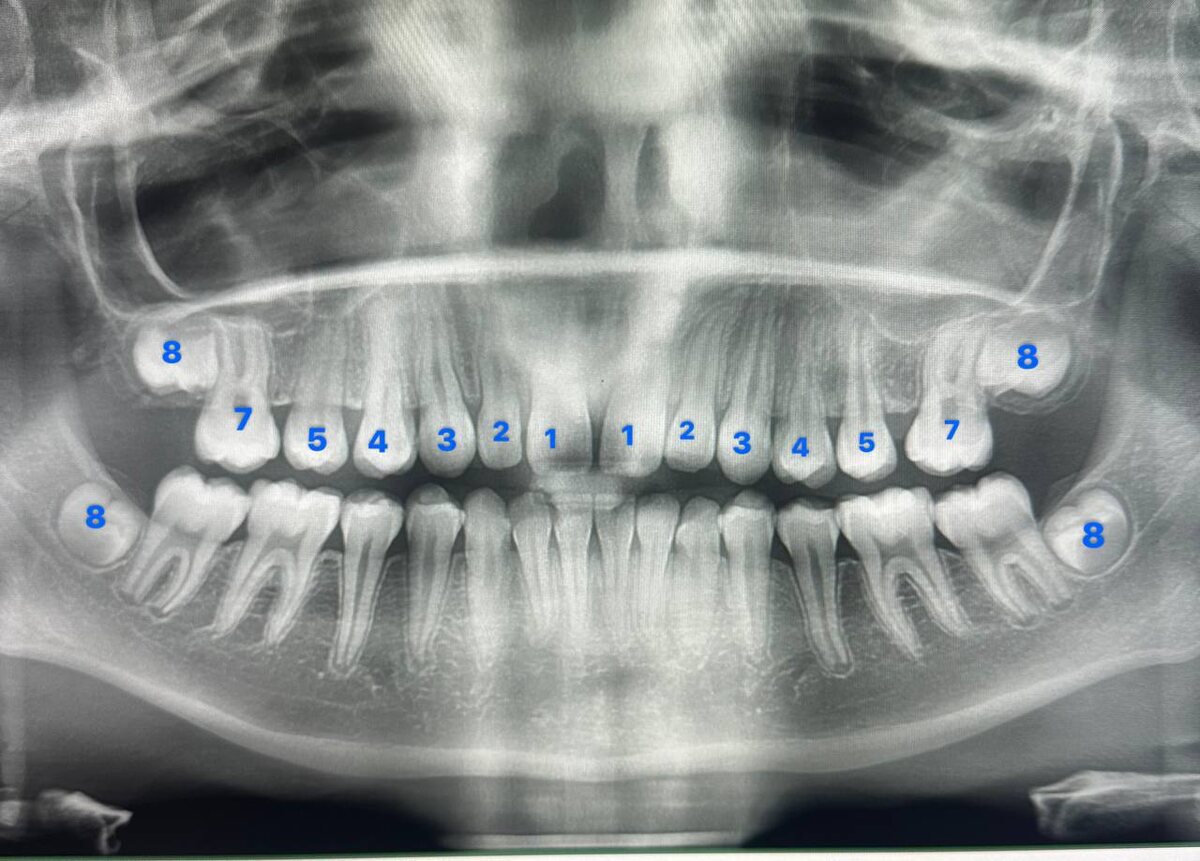

Чуть более пристальный взгляд разберет, что у данного пациента нет постоянных верхних шестых зубов. Сразу отмечу: не потому что их удалили, а потому что 😔 изначально не было зачатков.

🔜 Действительно, удивительные способности нашего организма к компенсации любых состояний сделали свое дело: вы практически не замечаете отсутствия шестых зубов.

🔜 Шестые зубы - первые моляры, крайне важны! Жевательная нагрузка будет распределяться неверно, что приведет к своим последствиям, в данном клиническом случае велик риск образования клиновидных дефектов.

🔜 Отсутствующие зубы достаточно крупные, поэтому между зубами образовались промежутки - тремы.

🔜 Пациента не устраивает эстетика